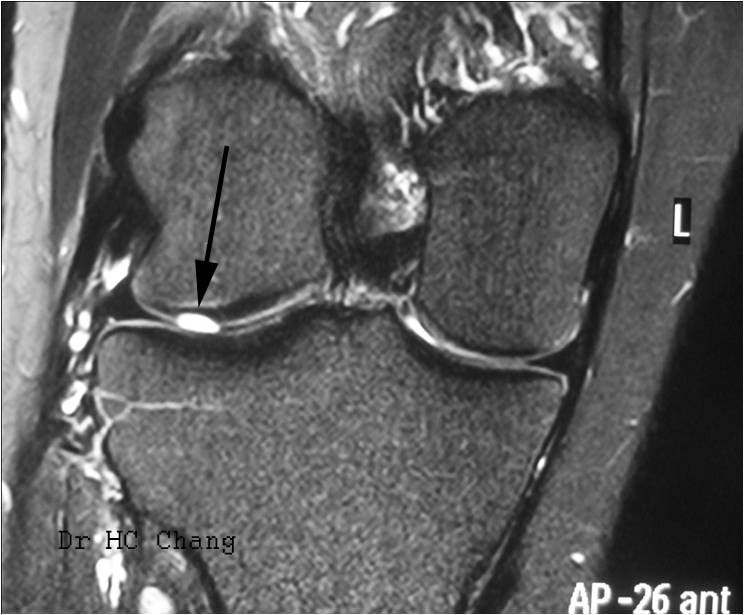

This is an MRI scan in a person who has knee pain and intermittent swelling. MRI confirmed a full thickness cartilage defect in the lateral femoral condyle.